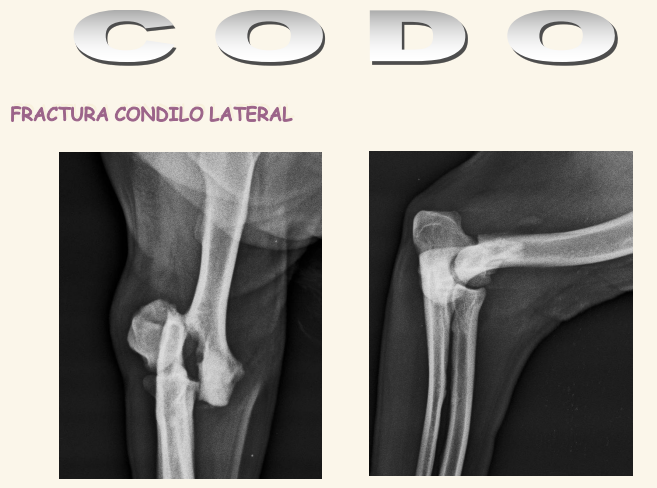

Codo

El condilo medial es mas fuerte que el lateral. Se dan fracciones en T o en Y. Luxacicones son mas dificiles que en codo